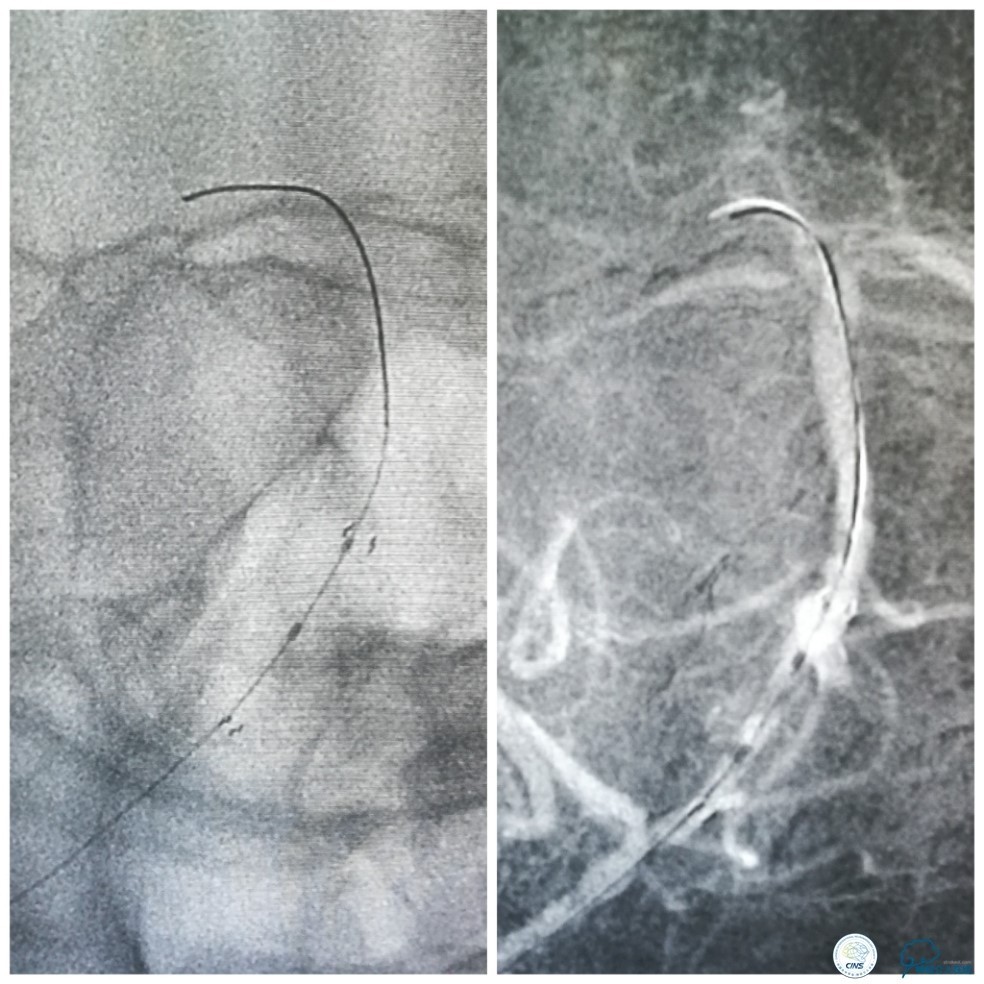

全麻下右侧股动脉穿刺置入8F动脉鞘,6F导引导管到位,送入Traxcess(0.014″200cm)微导丝+Echelon-10微导管小心通过右侧椎动脉V1段狭窄处至V2段远端,交换撤出Traxcess微导丝,送入Transend(0.014″300cm)微导丝至V2段远端(图10)。

图10

Ultra-Soft球囊(3.0mm×20mm)于狭窄处预扩张后置入EXCEL支架(4.0 mm× 24mm),球扩后造影见支架贴壁良好,远端血管显影好,前向血流TICI3级。6F导引导管沿微导丝通过右椎动脉V1段支架至V2段(图11)。

图11